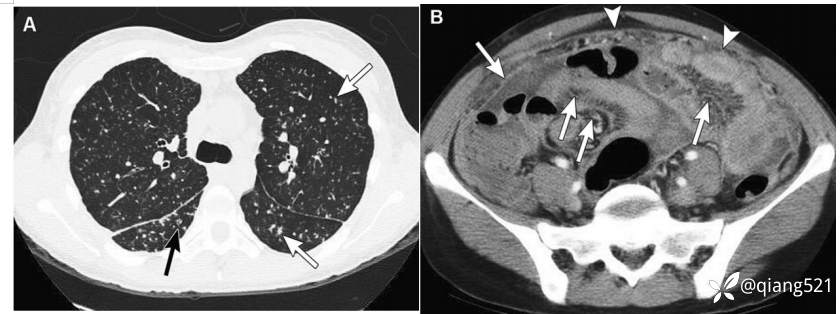

48岁妇女,患有肺结核。胸部轴位HRCT显示大量小结节(箭头),与粟粒性肺结核一致。B经下腹部的轴向CECT显示弥漫性腹膜和网膜增厚(粗箭头),肠系膜水肿/粘连(箭头)和轻度腹水(箭头),与结核性腹膜炎一致